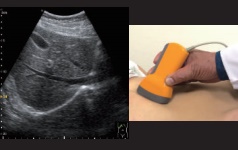

Made in JAPANの超音波画像観察装置

この製品は、発展途上国向けや教育現場向けに開発した超音波スキャナーです。

独自の機能、SyncView(シンクビュー)は撮影部位・角度をより感覚的に確認できます。

本機能を用いて撮像すると、走査 する手元の画像と超音波画像がセットで記録されます。

そのため、従来から使用されているボディーマーク機能に比べ、当 てている部位やプローブの角度がより簡単に確認できます。

当て方の参照が容易であることから、E-教材としての活用、復 習や意見交換、アドバイスを受ける際に役立ちます。